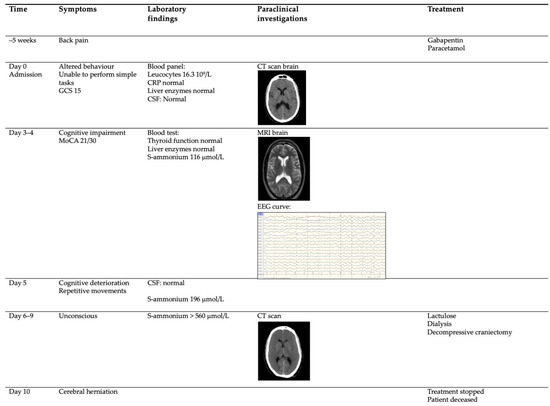

Hyperammonaemic Encephalopathy Caused by Adult-Onset Ornithine Transcarbamylase Deficiency

by Bjarke Hammer Niclasen, Maria Therese Schelde-Olesen, Mads Astvad, Anders Løkke, Thomas Krøigård and Helle H. Nielsen

Brain Sci. 2022, 12(2), 231; https://doi.org/10.3390/brainsci12020231 - 8 Feb 2022

Cited by 5 | Viewed by 4308

Hyperammonaemic encephalopathy in adults is a rare condition in the absence of liver disease and is associated with a high mortality and risk of permanent neurological deficits. Seldomly, the condition is caused by an inborn error of metabolism in the urea cycle, triggered [...] Read more.

Hyperammonaemic encephalopathy in adults is a rare condition in the absence of liver disease and is associated with a high mortality and risk of permanent neurological deficits. Seldomly, the condition is caused by an inborn error of metabolism in the urea cycle, triggered by an exogenic factor such as gastrointestinal haemorrhage, gastric bypass surgery, starvation, seizures, vigorous exercise, burn injuries, or drugs hampering the elimination of ammonia. Here, we present a fatal case of an unrecognized genetic ornithine transcarbamylase deficiency (OTCD) presenting with a subacute progressive encephalopathy. We review the current literature and discuss the differential diagnosis and treatment options. As swift diagnosis and initiation of treatment is vital, awareness of hyperammonaemic encephalopathy and its possible causes can help improve the prognosis of this condition. Full article